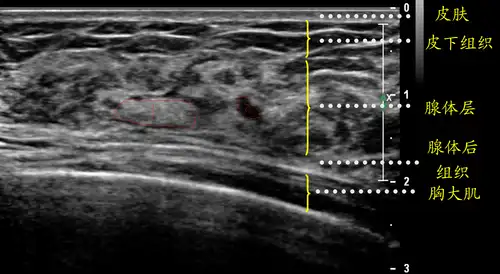

超声笔记乳腺基础

一张正常的乳腺b超图 - 超声医学讨论版 - 爱爱医医学论坛